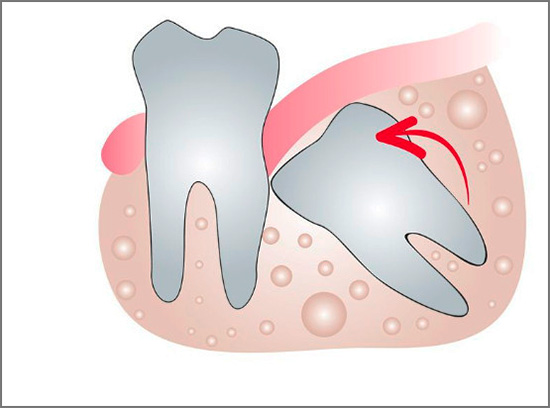

Quando dentano i denti del giudizio, spesso hanno una banale mancanza di spazio: possono crescere lateralmente e verso il vicino più vicino. In generale, i denti del giudizio inferiori sono i più problematici, poiché quando esplodono compaiono di solito uno o due tubercoli, ricoperti di una gomma, come un "cappuccio", sotto il quale, come in un "bidone della spazzatura", il cibo viene costantemente riempito e marcito.

I denti del giudizio crescenti (specialmente quelli inferiori) sono insidiosi nel senso che in oltre il 60% dei casi la mascella non è posizionata correttamente. Quasi sempre, l'inclinazione è orientata verso il settimo dente, il che crea molti problemi. Prima di tutto, è un dolore.

Spesso i denti inferiori della saggezza iniziano a tagliare e ferire, ma non hanno fretta di apparire sulla superficie delle gengive.Nelle immagini è possibile osservare come il dente "saggio" sia quasi in inclinazione orizzontale rispetto a quello adiacente, per cui in alcuni casi clinici inizia anche a provocare dolore. Anche nel dente del giudizio che non è ancora apparso sulla superficie delle gengive, possono verificarsi carie e sue complicazioni, poiché i batteri cariogeni passano facilmente sotto la gomma dietro il penultimo "sette".